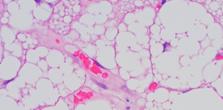

Immediately upon exposure to a cold environment, our bodies enter their 'fight or flight' response, commonly termed increased sympathetic nervous system activity. This response stimulus activates brown adipose tissue (BAT) [8], which is responsible for thermogenesis and producing heat in response to a cold environment and increasing energy expenditure [5]. Much research has been published on brown adipose tissue in mice, with little research in humans. This is primarily due to the technical difficulty in measuring its activity but also due to the limited depots of BAT in humans, which are only located in small amounts around the clavicles, upper back, and spine [9] (see PET CT scan below).

"Brown fat is a type of fat that generates heat by burning calories. It contains a lot of mitochondria, which give it a brown colour and help produce energy. Its main role is to regulate body temperature and keep us warm. It is found in small amounts in adults, mostly in the neck and upper back. White fat is the most common type of fat in our bodies. Unlike brown fat, white fat doesn't produce much heat. Excess white fat can lead to obesity and health problems. It is located under the skin (subcutaneous fat) and around organs (visceral fat)."